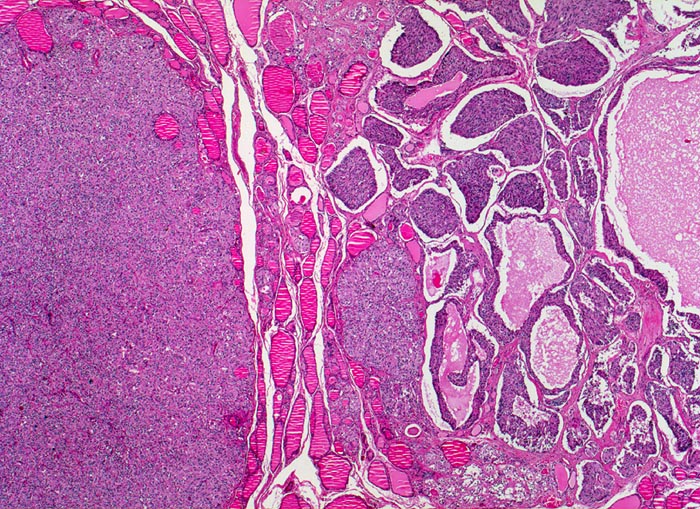

Basel 1MA/ Medulläres Schilddrüsenkarzinom

Medulläres Schilddrüsenkarzinom

• Mehrere, unscharf begrenzte, unbekapselte Tumorknoten mit desmoplastischem Stroma in ansonsten unauffälligem Schilddrüsenparenchym.

• Die Tumorinfiltrate bestehen aus soliden und kribriformen Verbänden spindeliger Tumorzellen.

• Mehrere Herde hyperplastischer C-Zellen im nicht-neoplastischen Schilddrüsenparenchym als möglicher Hinweis auf ein hereditäres medulläres Schilddrüsenkarzinom.

• Tumorzellen mit überwiegend monomorphen Zellkernen mit feinkörnigem Pfeffer und Salz Chromatin (Merkmal endokriner Zellen). Nukleolen sind nicht prominent. Reichlich eosinophiles Zytoplasma.

• Kleiner Lymphknoten mit Metastase des medullären Schilddrüsenkarzinoms. Das sollte der Kliniker dem Pathologen mitteilen: